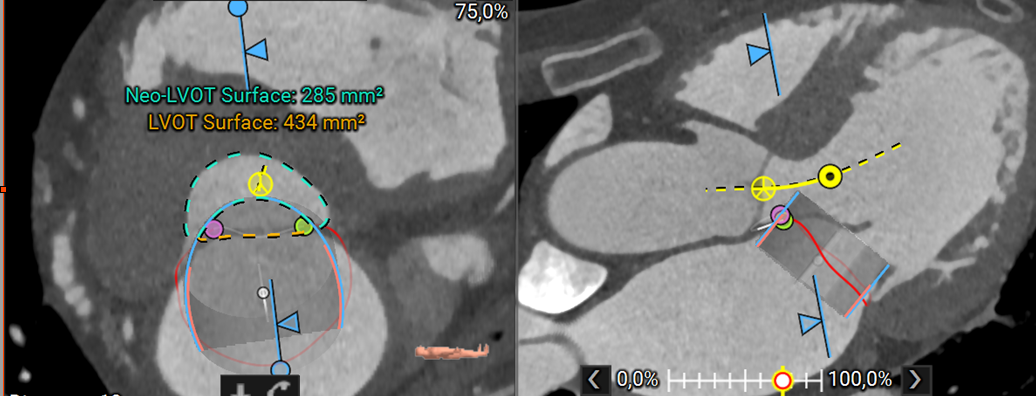

1. Cardiac CT plays a central role by providing detailed measurements of the mitral annulus, assessing the predicted neo-LVOT area to avoid left ventricular outflow tract obstruction, and identifying calcium distribution across the annulus and leaflets.

Planning software like 3mensio Structural Heart can can streamline TMVR planning by providing accurate annular sizing, neo-LVOT area prediction, assessment of annular and sub-annular calcification, and simulation of both transapical and transseptal access paths. This comprehensive imaging and planning workflow enables device selection, positioning, and risk management, particularly in anatomically challenging cases.